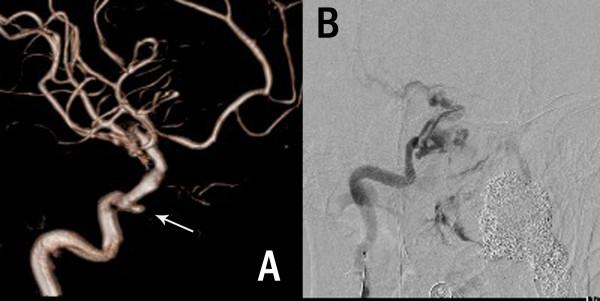

Three cases of intracranial angioleiomyoma (ALM) in our neurosurgery center are reported in detail. ALM is a benign soft tissue tumor comprised of mature smooth muscle cells and a prominent vascular component, which is extremely rare as a primary intracranial lesion. Altogether, only 12 cases were recorded in the literature to date, to the best of our knowledge. Case 1 is the second report of intra-sella ALM, a 51-year-old woman presented with visual deterioration for 2 months. An MRI showed an intra-sella 3-cm tumor, partially flame-like, enhanced with gadolinium. Using microscopic endonasal transsphenoidal approach, the tumor was completely resected with great difficulty. At 11 days post-surgery, she died of a sudden catastrophic nasal hemorrhage. An angiography revealed a pseudo-aneurysm of ICA (internal carotid artery). Case 2 is a 49-year-old man who presented with weakness of the lower limbs for 1 year. A large subtentorial mass was found affixed to the torcular and straight sinus, which was partially flame-like, dramatically enhanced as in case 1. Case 3 is that of a 77-year-old man. An ALM mass was revealed in the diploe of left temporal bone, and had eroded the inner table. Immunohistochemical workup confirmed the diagnosis of angioleiomyoma in all 3 cases. The radiology, operation, and complication of surgery in each case were discussed. In conclusion, intracranial ALMs are extremely rare, usually located ex-neuro axis (such as in our cases), in the sella, in posterior fossa, or in the skull. Magnetic resonance imaging (MRI) revealed a special feature of flame-like partial enhancement that may be helpful to distinguish ALM from pituitary tumors or meningiomas, and should result in the consideration of this rare tumor entity early on in the diagnostic process. A definitive diagnosis depends on histological analyses. The resection of ALM in certain locations is difficult and risky because of the rich blood supply.